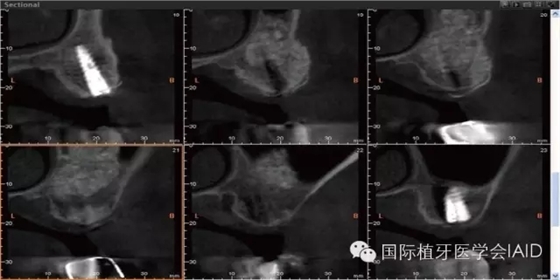

初期穩(wěn)定度在第一及第二類型的案例(>9mm; 6mm-9mm) 可以較容易達(dá)到,故通常以crestal approach進(jìn)行手術(shù)。Lateral window術(shù)式在第三型(3mm-6mm)較被建議。 若是前三個(gè)類型的初期穩(wěn)定度達(dá)到35Mpa,可以考慮當(dāng)次放置植體。若骨頭條件屬于第四型(<3mm),Lateral approach 比較建議使用,而植體可考慮等到Grafted Bone較成熟時(shí)再置入。(Fig. 1 & 2)術(shù)式的選擇與骨頭高度有密切的關(guān)系,當(dāng)骨頭垂直高度小于3 mm(于兩顆植體中),植體應(yīng)考慮 Bone graft穩(wěn)定后再植入。

Lateral window的區(qū)域及范圍可借由CBCT和解剖構(gòu)造位置來決定。理想的window骨切線前緣及下緣位置應(yīng)離sinus底部(floor)其前緣(anterior wall)3-5 mm (Fig. 5 & 6)。

上緣不能高于后上齒槽動脈(上頜動脈分支),而后緣應(yīng)由植體位置所決定。 當(dāng)預(yù)定好切骨頭位置決定后,先在牙脊上軟組織做一條水平切線,這條水平切線需切足,以暴露出手術(shù)區(qū)域(Fig. 7)。 水平切線完成后,在皮瓣的近心處做一條垂直切線(Fig. 8),接著進(jìn)行全層瓣(Full-thickness)的翻瓣。當(dāng)上頜骨側(cè)方暴露出來后,可以使用牙周探針測量手術(shù)前決定的骨切除位置。測量及決定實(shí)際位置后,可使用超聲骨刀(Piezoelectric)或旋轉(zhuǎn)器械(Rotary instruments)進(jìn)行側(cè)窗的骨切除。當(dāng)骨切線完成,并可以完整地看到上頜竇膜(sinus membrane)時(shí)(Fig. 9),骨側(cè)窗需輕巧地推入上頜竇腔內(nèi)(Fig. 10),并小心地將sinus membrane跟骨頭游離開(Fig. 11)或?qū)]支撐的骨頭完全移除 (Fig. 12)。